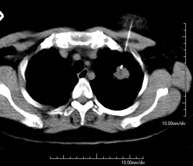

Prova diagnòstica que consisteix en obtenir imatges del tòrax d'alta definició anatòmica (pulmons, cor, mediastí, grans vasos, caixa toràcica, etc. ) mitjançant l'ús d'un equip de TC (Tomografia Computeritzada). Aquestes imatges s'estudien posteriorment en una estació de treball que permet reconstruccions bidimensionals en diferents plànols de l'espai i també reconstruccions 3D (volumètriques). Alguns estudis requereixen l'ús de contrast iodat per millorar la definició de les imatges. - Angio –TC Aorta toràcica

Prova que consisteix en obtenir una mostra de teixit de lesions toràciques, com per exemple masses pulmonars, mediastíniques, lesions òssies, etc. Per això s'administra anestèsia local sobre la zona de punció, que es realitza amb agulles de calibre fi. Tot el procediment es realitza controlat amb imatges obtingudes per tomografia computaritzada (TC) en diversos moments de la punció, mitjançant un equip de Fluoroscòpia-TC. Després de la prova, el pacient resta unes hores hospitalitzat. És necessari portar proves de coagulació abans de la punció. - Biòpsia tòrax guiada per TC

Consisteix en obtenir una mostra de teixit d'una determinada lesió toràcica, com per exemple del pulmó, del mediastí, de l'estern, etc. A vegades es realitza sota sedació, amb l'ajuda de l'equip d'anestèsia. S'utilitzen agulles que permeten l'obtenció d'un cilindre de la lesió a estudiar que s'enviarà a Anatomia Patològica per a la seva anàlisi histològica. Tot el procediment es realitza controlat amb imatges obtingudes per tomografia computaritzada (TC) en diversos moments de la biòpsia, mitjançant un equip de Fluoroscòpia-TC. Després de la prova, el pacient resta hospitalitzat per controlar la seva evolució. És necessari portar proves de coagulació abans de la punció. - TC Columna Dorsal